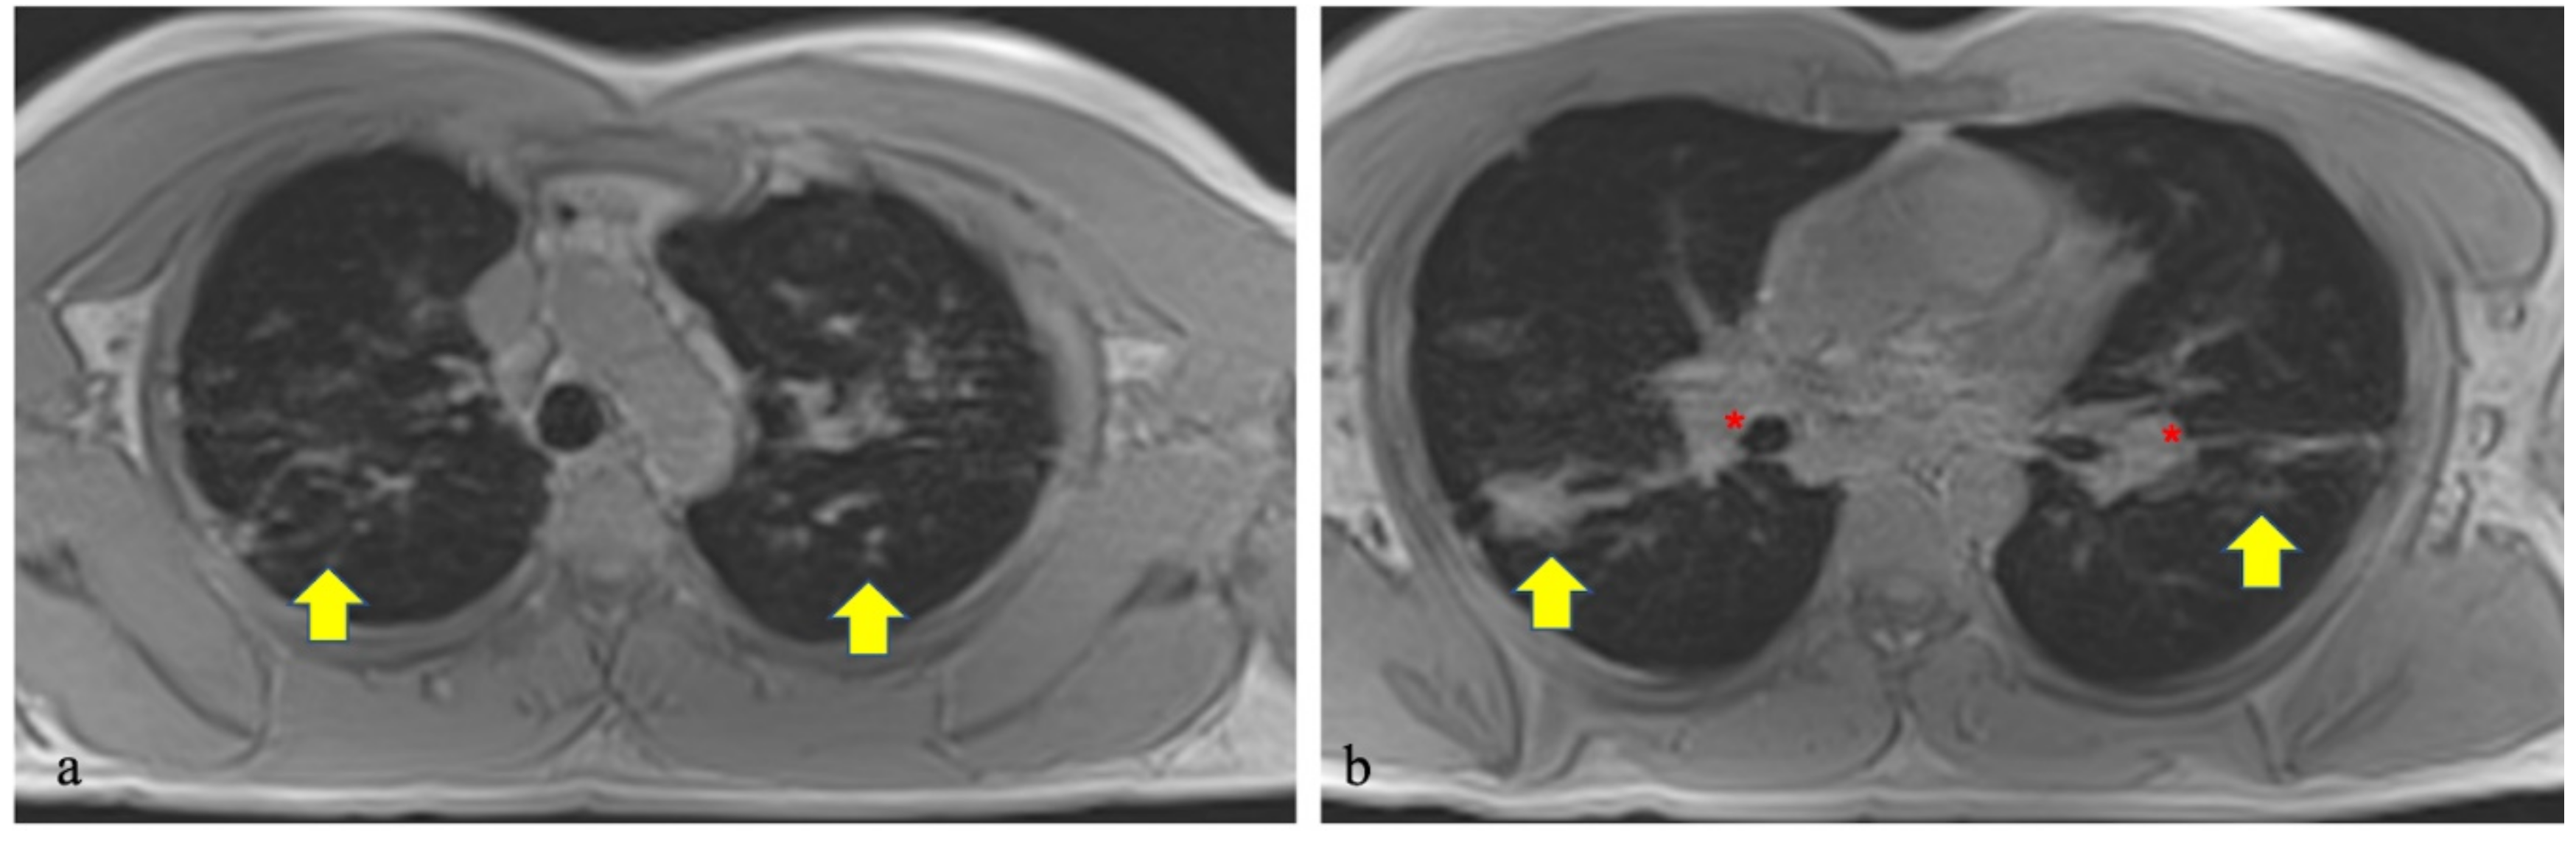

- Ekinci, A.; Yucel Ucarkus, T.; Okur, A.; Ozturk, M.; Dogan, S. MRI of pneumonia in immunocompromised patients: comparison with CT. Diagn. Interv. Radiol. 2017, 23, 22–28. [Google Scholar] [CrossRef]

- Yan, C.; Tan, X.; Wei, Q.; Feng, R.; Li, C.; Wu, Y.; Xu, Y. Lung MRI of invasive fungal infection at 3 Tesla: Evaluation of five different pulse sequences and comparison with multidetector computed tomography (MDCT). Eur. Radiol. 2014, 25, 550–557. [Google Scholar] [CrossRef] [PubMed]